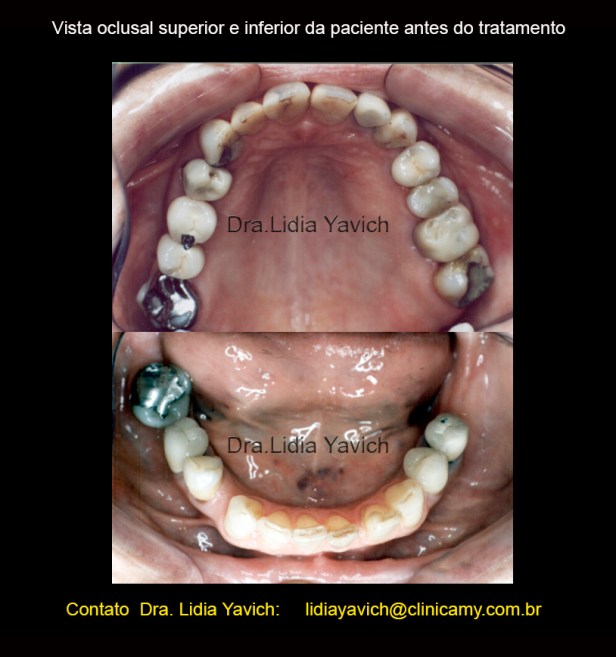

A vista oclusal dos dentes da paciente é marcada pelo desgaste dos dentes anteriores, tanto superiores como inferiores.

Ao exame radiográfico obseva-se ausência dos elementos dentais 18,16,28,28,36, 46 4 48.

Os elementos 15, 14, 22, 24, 26, 35,44 e 45 se encontram endodonticamente tratados.

Presença de prótese fixa com apoio nos elementos 16/15. Presença de prótese fixa unitária com pino metálico intracanal nos elementos 14, 22, 26, 35,34 e 45.

Extensa restauração coronária nos elementos 13,24 e 44.

Presença de material restaurador nos elementos 11, 21, 23, 27,32 e 47.

Perda óssea alveolar na maxila e na mandíbula mais acentuada nas áreas edêntulas.